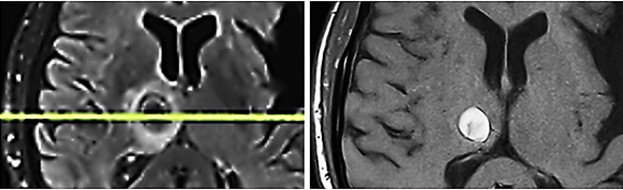

Case B

A now 76 years-old female patient suffered since 2013 from a metastatic malignant superficial spreading skin melanoma (pT3aN3cM1c) in the right gluteal area. After resection of the primary tumor and repetitive resections of cutaneous and subcutaneous metastases situated between the primary tumor and the regional lymph nodes (in-transit filiae), and metastases in the regional lymph nodes, and after immunotherapy cycles with Nivolumab, in 2020, an occipital brain metastasis occurred. Nivolumab immunotherapy was resumed, applying 25 cycles. Five extracorporeal TMI treatments (4, 000 impulses each within 20 minutes) were applied to a cutaneous metastasis. As well the treated tumor as the not treated metastases regressed significantly. In June 2024, transcranial TMI treatment of a new occipital metastasis was applied. The treated brain-metastasis regressed. Controls six, twelve and twenty months, the latter in February 2026, after transcranial TMI treatment did not show any new metastases and no vital tumor tissue in the glial scar remnants of the regressed metastasis (Fig. 6).

Fig. 6

Fig. 6: Occipital metastasis six months (left) and twelve months (right) after transcranial TMI treatment with glial scar. Notably the brain tissue is not impaired by the transcranial TMI treatment